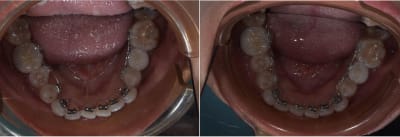

Et le suivi du patient collé il y a trois semaine. Je l'avais posté sur ce fil

https://www.eugenol.com/sujets/419256-alternative-a-invisalign-2d-et-autre?page=2#lg=1&slide=0

Grosse plainte de la patiente car les dents on fait mal, le soft flow est tombé et elle n'aime pas les cales de surocclusion.

j'ai du lui expliquer gentiment qu'en vestibulaire ça aurait était la même chose en moins confortable, des limitations au niveau de l'alimentation et une hygiène plus dure à maintenir.

Ma patiente revue une dixaine de jours après la pose du niti 18 en haut et niti 16 en bas.

Elle repart en Europe se soir avec les impression 3D et le fil préplier.

Je dois dire que pour 9 semaine de traitement pas de quoi avoir honte , et je doute que ça eu était meilleur avec invisalign